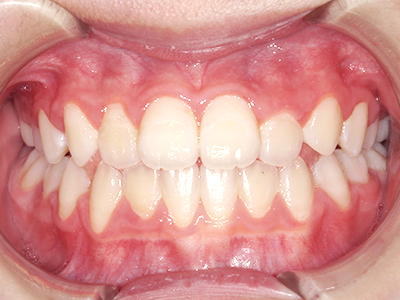

歯並びやかみ合わせを正しく整えると、笑顔や発音の自信につながり、むし歯・歯周病・口臭の予防にも役立ちます。

ないき歯科クリニックでは、上あごの成長不足を補い、鼻呼吸を獲得しつつ歯列を整え、将来のお口をより健康な状態にすることをゴールに定める矯正治療をおこなっています。

【4】矯正治療

矯正装置を装着し、調整しながら少しずつ歯を移動させ、歯並びを整えていきます。